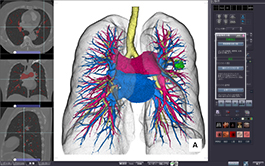

CT PA/PV AUTO-SEGMENTATION

This standard feature allows you to display lungs, bronchi, pulmonary artery and pulmonary veins simultaneously. Click on an individual structure to toggle its inclusion in the arterial or venous mask. Fusion of structures such as lesions or tumors is straightforward.

CT LUNG RESECTION PLANNING

High precision automatic segmentation of lungs, lung lobes, bronchi, pulmonary arteries and veins enable lung resection proposals based on bronchial or arterial anatomy.